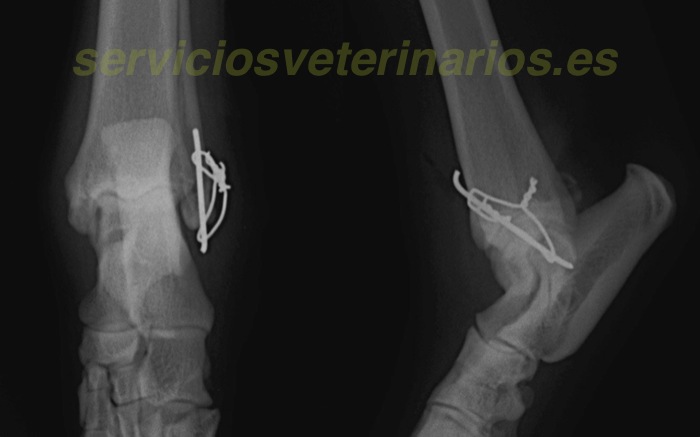

| Tratamiento | Tras comprobar que el motivo de la inestabilidad está en una fractura ósea sobre el extremo del maleolo, punto de inserción ligamentoso, se cambia el procedimiento inicial para lesión ligamentosa (tres tornillos y ligamentos artificiales de poliéster ) a un procedimiento para esta fractura con aguja y banda de tensión. |

Finalmente se coloca una aguja de Kirshner de 1,6 mm que atraviesa inicialmente y de forma anterógrada el fragmento proximal, tras comprobar que el punto de salida es central al área de fractura se comprimen ambos extremos de la fractura con una pinza de hueso y se clava la aguja hasta salir por el fragmento distal.

Se prepara una banda de tensión con las alas para ser rotadas fácilmente. El alambre así tensionado ejercerá la misma fuerza en ambos lados. Una vez ajustada la fuerza, con cuidado para no fracturar el pequeño fragmento distal, se cortan y rotan internamente los extremos.

Se deja con férula durante 3 semanas para evitar tensiones excesivas de manera prematura ya que el peso cercano a 30 kg puede ejercer demasiada fuerza para el pequeño fragmento distal. El apoyo es correcto al retirar la férula así como las radiografías y exploraciones. Aun así se limita la actividad un mes mas.